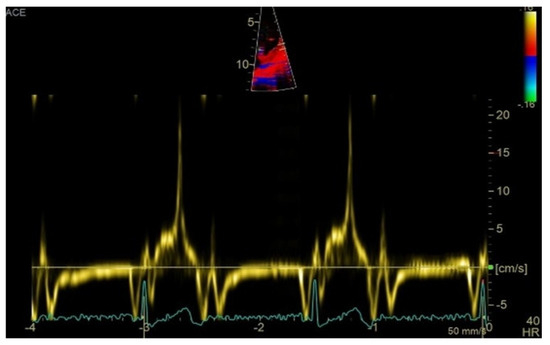

Transthoracic echocardiography revealed myxomatous degeneration of the mitral valve with bileaflet redundancy, increased leaflet length and thickness, and prolapse of both leaflets. Notably, a mitral annular disjunction (MAD) measuring 10 mm was observed in the parasternal long-axis view at end-systole (Figure 2A–C). Additionally, systolic “curling motion” of the posterolateral wall of the left ventricle was present, and the Pickelhaube sign was documented (Figure 3).

High-velocity spike (21 cm/s) between mid-systole to late-systole using tissue Doppler imaging on the lateral mitral annulus. Known as the Pickelhaube sign, this sharp annular spike resembles the spike that adorns the Pickelhaube helmet, historically worn by the German military. It has been proposed as a marker of arrhythmogenic mitral valve prolapse.

Comprehensive echocardiographic assessment is crucial [4,61] and should include evaluation of mitral valve morphology and mitral annular diameter [62]. Mitral annular dilatation and flattening are frequently associated with mitral annular disjunction, which should be evaluated in terms of presence and length. A distinct echocardiographic feature—termed the “Pickelhaube sign”—described by Muthukumar et al. [63], represents a sharp mid-to-late systolic velocity spike at the lateral mitral annulus seen on tissue Doppler imaging, and has been proposed as a marker of arrhythmogenic mitral valve prolapse.